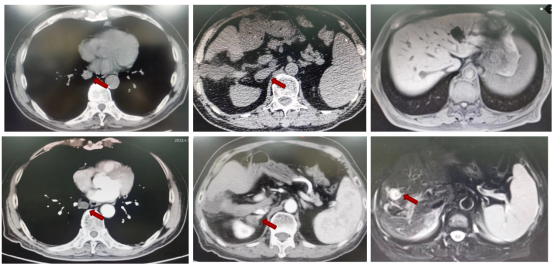

盆腔MRI(2021年04月26日):1.直肠管壁及周围改变,考虑中位直肠癌:T4aN2,CRM(阳性),EMVI(阳性)(图1)。

图1 2021年04月26日盆腔MRI